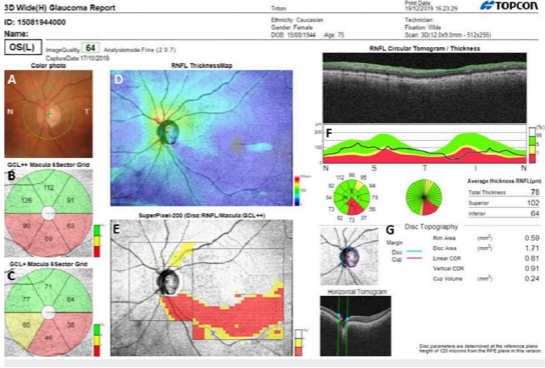

Our approach to glaucoma is proactive and vigilant. Through regular monitoring and advanced treatment options, we are able to ensure that you maintain your vision and enjoy a vibrant life free from the limitations of this silent threat.

Ophthalmology requires a lot of technology because the eye is both small yet incredibly complex, with 80% of external input to the brain processed by the visual system. For example, some eye diseases like diabetic eye disease can cause thickening in the nerve layer measured in micrometers.

Technology aids clinical eye examination in diagnosis and monitoring of your eye condition by taking away the subjectivity through precise measurements and grading. The powerful imaging technology we have also allows our patients to better visualise and understand their condition. We also employ technology for treatment and surgery to bring about our aim of good outcomes and quicker recovery.

The DRI OCT Triton combines the world’s first Swept Source OCT technology with

The DRI OCT Triton combines the world’s first Swept Source OCT technology with

multimodal fundus imaging. Using Swept-Source technology allows visualization into the deepest layers of the eye – even through cataracts, hemorrhages, gas bubbles, and other media opacities.The fast 100 kHz scanning speed and invisible scan beam rapidly capture detailed images, resulting in fewer motion artifacts and stunning image quality.

The DRI OCT Triton combines the world’s first Swept Source OCT technology with multimodal fundus imaging. Using Swept-Source technology allows visualization into the deepest layers of the eye – even through cataracts, hemorrhages, gas bubbles, and other media opacities.The fast 100 kHz scanning speed and invisible scan beam rapidly capture detailed images, resulting in fewer motion artifacts and stunning image quality.

Diagnostic capability Seeing deeper makes it possible to have a better understanding of many ocular pathologies2. With features such as OCT Angiography1, Fundus Autofluorescence* and En Face OCT, Triton empowers clinicians with multimodal imaging capability to help assess and preserve patient’s eye health.